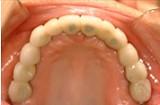

问题 多基牙长桥,最好的取得共同就位道的方法是()

选项 A.取研究模型,在观测仪上观察分析,设计确定就位道 B.每个牙按照各自单冠预备要求预备 C.口内观察基牙形态位置 D.以上都不对 E.以上方法均可

答案 A